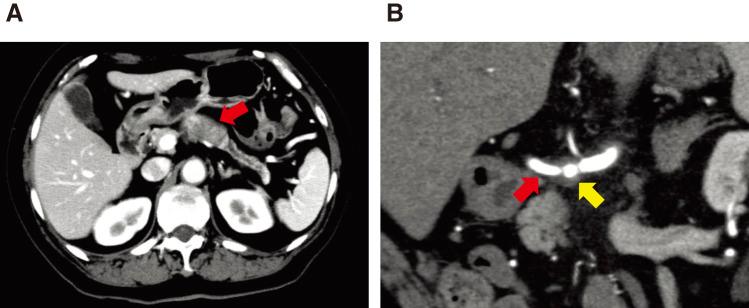

The patient was a 69-year-old woman with a pancreatic tumor that was detected with computed tomography (CT) during a postoperative colon cancer checkup. She was suspected of having pancreatic body cancer without distant metastasis. Distal pancreatectomy with celiac axis resection was performed. Postoperative pathological examination revealed an invasive ductal adenocarcinoma with lymph node metastasis (pT4N1M0, stage III). Postoperatively, she received adjuvant chemotherapy containing gemcitabine and S-1 for 1 year and 4 months, and S-1 monotherapy for 1 year. Six years and 2 months after the initial surgery, her serum carbohydrate antigen 19-9 level elevated, and CT revealed soft tissue in front of the left kidney. Positron emission tomography/CT also revealed high fluorine-18 fluorodeoxyglucose uptake in the tissue. Accordingly, the patient was diagnosed with dissemination of PDAC. The patient was administered chemotherapy with gemcitabine and S-1. One year and 6 months after the diagnosis of dissemination, CT revealed reduction of the nodule. Therefore, we decided to eliminate this dissemination. A left nephrectomy and partial gastrectomy were performed. Histopathological examination confirmed dissemination of PDAC. The patient refused adjuvant chemotherapy. No evidence of recurrence has been observed for 13 years and 3 months since the initial surgery, and 5 years and 1 month since the resection of the dissemination.

该患者为一名69岁女性,在结肠癌术后检查时通过计算机断层扫描(CT)发现胰腺肿瘤。怀疑患有胰体癌且无远处转移。进行了伴有腹腔干切除的远端胰腺切除术。术后病理检查显示为浸润性导管腺癌伴淋巴结转移(pT4N1M0,Ⅲ期)。术后,她接受了含吉西他滨和S-1的辅助化疗1年零4个月,以及S-1单药治疗1年。初次手术后6年零2个月,她的血清糖类抗原19-9水平升高,CT显示左肾前方有软组织。正电子发射断层扫描/CT也显示该组织中氟-18氟脱氧葡萄糖摄取高。因此,该患者被诊断为PDAC播散。给予患者吉西他滨和S-1化疗。播散诊断后1年零6个月,CT显示结节缩小。因此,我们决定切除这种播散灶。进行了左肾切除术和部分胃切除术。组织病理学检查证实为PDAC播散。患者拒绝辅助化疗。自初次手术以来13年零3个月,以及自播散灶切除以来5年零1个月,均未观察到复发迹象。